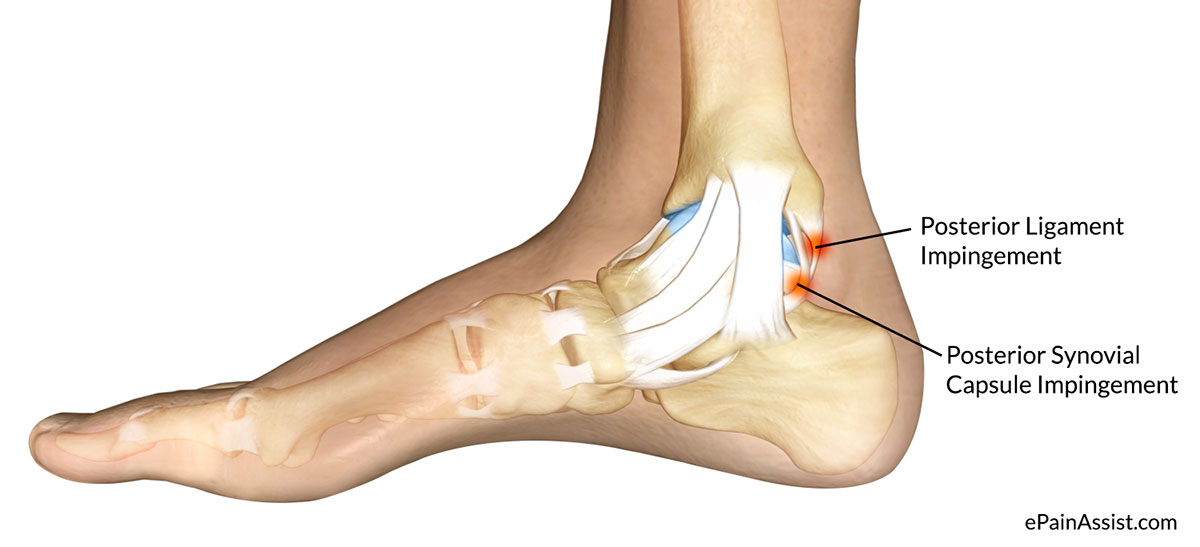

Тендинит Ахиллова сухожилия: симптомы и лечение

Раздел: Картинки на заметку